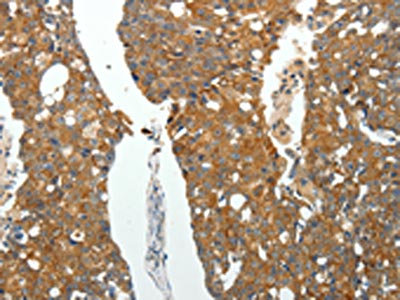

The image on the left is immunohistochemistry of paraffin-embedded Human breast cancer tissue using CSB-PA057038(ROCK1 Antibody) at dilution 1/25, on the right is treated with fusion protein. (Original magnification: ×200)

The image on the left is immunohistochemistry of paraffin-embedded Human gastric cancer tissue using CSB-PA057038(ROCK1 Antibody) at dilution 1/25, on the right is treated with fusion protein. (Original magnification: ×200)